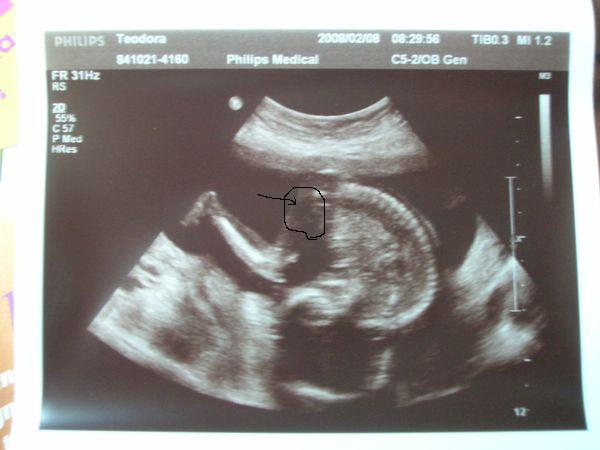

Ide is felrakom a régi uh képet..... ma nézegettem. Mintha látnék rajta valamit!! Vagy csak káprázik a szemem!!

Dodó! Szerintem nem káprázik a szemed! Ez lehet........!!! :D :D :D :D